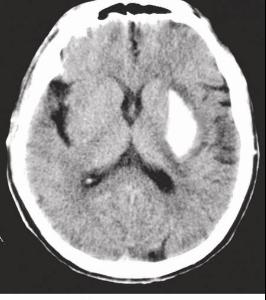

肝硬化并發(fā)癥都在這,看看你有沒有肝病#。肝硬化患者一旦出現(xiàn)以下四種并發(fā)癥你就要注意肝硬化并發(fā)癥#。還不重視肝硬化,二大并發(fā)癥很致命。肝硬化會(huì)帶來的并發(fā)癥一個(gè)都不簡單。第二是肝性腦病,肝性腦病是肝硬化非常嚴(yán)重的并發(fā)癥之一,通常是肝硬化患者死亡的直接原因。

所以在肝硬化的治療期間,要針對肝性腦病進(jìn)行預(yù)防性治療。專家提示:肝硬化最常見的并發(fā)癥是食道靜脈曲張破裂引起的消化道大出血,也是最兇險(xiǎn)的一種并發(fā)癥,嚴(yán)重會(huì)危及患者生命;部分患者會(huì)出現(xiàn)肝腎綜合征、肝肺綜合征或肝性腦病,都是常見的并發(fā)癥;另外,肝硬化患者還可能出現(xiàn)肝癌,因此肝硬化的患者一定要定期到門診復(fù)查。

所以如果查出肝硬化之后一定要積極的進(jìn)行治療,延緩病情的進(jìn)展,否則等到危及生命再進(jìn)行治療就晚了。肝硬化算不算大病?有很多乙肝朋友問,肝硬化算是大病嗎,其實(shí)肝硬化是肝病的終末期階段,是由于肝功能長期持續(xù)受損導(dǎo)致肝臟形態(tài)的改變,嚴(yán)重的話也會(huì)出現(xiàn)肝腹水、肝性腦病、消化道出血等一系列的并發(fā)癥,不僅僅會(huì)影響生活的質(zhì)量,甚至?xí)绊懮?/p>